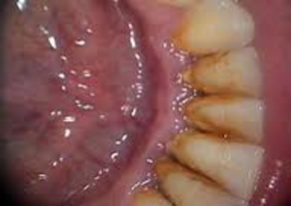

Şi când mă gândesc că acum merg la dentist fără să-mi fie frică nici nu-mi vine să cred. Cum am spus la început am făcut detartraj pentru că gingia mea era foarte umflată, iar la periaj îmi sângera câteodată. Astăzi am aflat că tartrul se face şi din cauza salivei şi a mineralizării plăcii bacteriene. Pe limba mea de neştiutoare şi din ce am observat azi tartrul are un aspect de piatră de culoare închisă spre negru ce îl putem vedea la baza gingiei lipită pe dinte. În timp ce Bogdan (stomatologul meu) se chinuia să cureţe tartrul simţeam pe limbă firicele de nisip ca mai târziu acesta să-mi arate o bucăţică de tartru.

Şi am uitat să vă spun dacă aveţi senzaţia că nu v-aţi spălat suficient sau că aveţi un miros ciudat în gură să ştiţi că este tot de la tartru, după ce am scăpat de el mă simţeam cam goală, simţeam apa pe peste tot aveam senzaţia că îmi ajunge la rădăcina dinţilor, oricum a fost bine merită să aveţi puţină grijă şi de gingi nu numai de aspectul dinţilor din exterior. Eu sper să termin cât mai repede cu stomatologul să mă pot bucura de dantura mea (aia pe care o mai am).